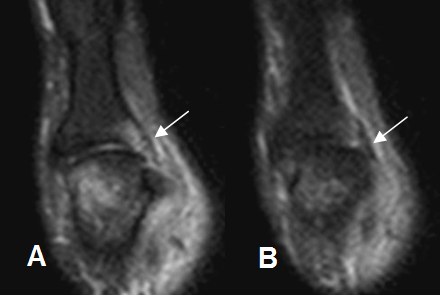

Fig 62 B. Lesión ligamentaria colateral.

A y B: RM coronal en STIR. Contusión de la falange proximal. Hay cambios inflamatorios rodeando el ligamento colateral lateral, el cual permanece íntegro, por esguince GI.